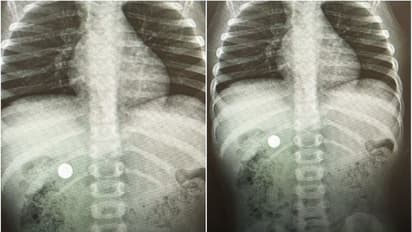

മനാമ: ബഹ്റൈനില് മൂന്നുവയസ്സുകാരിയുടെ വയറ്റില് നിന്ന് നീക്കം ചെയ്തത് ബട്ടണ് ബാറ്ററി. റിഫയിലെ സ്ത്രീകള്ക്കും കുട്ടികള്ക്കും വേണ്ടിയുള്ള റോയല് ഹോസ്പിറ്റലിലെത്തിച്ച കുട്ടിയെ വിദഗ്ധ പരിശോധനയ്ക്ക് വിധേയമാക്കിയപ്പോഴാണ് വയറ്റില് ബട്ടണ് ബാറ്ററി കണ്ടെത്തിയത്.

പീഡിയാട്രിക് ഗ്യാസ്ട്രോ എന്ട്രോളജി കണ്സള്ട്ടന്റ് ഡോ. സൗഹേല് ഷബീബിന്റെ നേൃത്വത്തിലുള്ള മെഡിക്കല് സംഘമാണ് കുട്ടിയുടെ കുടലില് നിന്നും എന്ഡോസ്കോപി വഴി ബാറ്ററി പുറത്തെടുത്തത്. ബട്ടണ് ബാറ്ററി കുടലിന്റെ ഭിത്തിയില് ഒട്ടിപ്പിടിക്കുകയും ഇതില് നിന്നുള്ള ഇലക്ട്രിക്കല് ലോഡ് പുറന്തള്ളുകയും ചെയ്യാന് സാധ്യതയുണ്ടെന്നും അങ്ങനെ തുടരുകയാണെങ്കില് ക്രമേണ കുടലില് പൊള്ളലുണ്ടായി സുഷിരം വരെ വീണേക്കാമെന്നും ഡോ. ഷബീബ് പറഞ്ഞു.